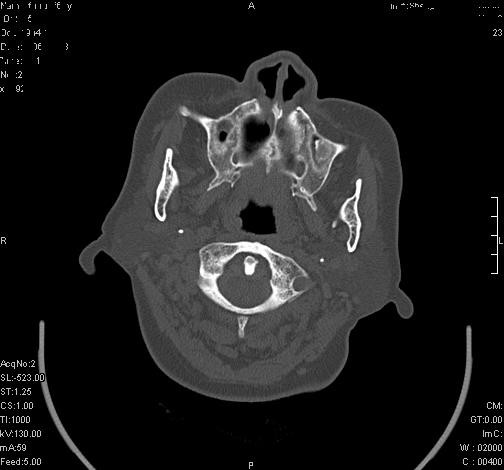

上次发的片子,不够细微。误导了大家,请大家再重新看一下,思路会更清晰。

双上颌窦高密度,其内见水样密度.考虑双上颌窦骨瘤伴上颌窦炎.

双上颌窦高密度,左侧病灶下部与左上颌窦底部骨质相延续,支持双上颌窦骨瘤

双侧上颌窦上部黏膜明显增厚、窦腔缩小,偏后侧窦壁骨质毛糙、模糊,窦腔内见条块状钙化。结合双侧鼻甲黏膜明显增厚,以及临床症状,

考虑:双侧上颌窦霉菌性鼻窦炎

双侧上颌窦密度增高,粘膜增厚,内见条片状钙化,窦壁无增生与破坏征象,双侧鼻甲粘膜肥厚.

意见:双侧霉菌性上颌窦炎.

温习:真菌性鼻旁窦ct特征 1)非侵袭性病变者可涉及到鼻腔和鼻窦,多为单侧,上颌窦最多见.2)ct示窦腔内软组织增生影,可呈息肉状,+c可强化3)增生软组织影内可见散在斑片状或沙砾状钙化区,此为其典型特点,4)

非侵袭性病变可见窦壁骨质增生,破坏少见;侵袭性病变可见窦壁骨质破坏.